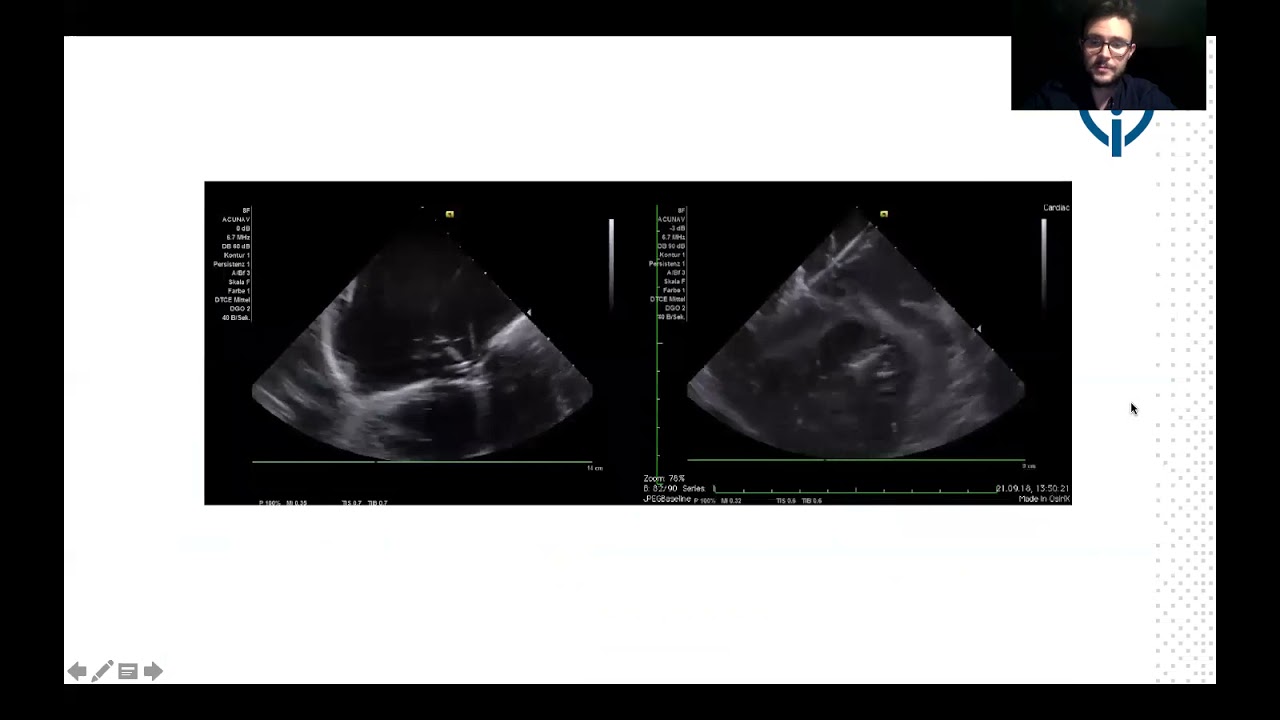

Percutaneous device closure of ruptured sinus of Valsalva: feasibility of transthoracic echocardiography-assisted procedure

By: Arvind Balaji, All India Institute of Medical Sciences, New Delhi, India